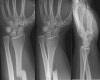

X-ray : 갈레아찌 골절(Galeazzi fracture)

척골 골절이 동반되지 않은 요골의 중간 및 원위부의 1/3 경계에서 발생되는 골절로서 원위 요척관절(DRUJ)의 탈구를 동반한 골절입니다.

다른 전완부 골절과 마찬가지로 X-ray 촬영시 주관절로 완관절을 포함합니다.

X-ray만으로도 쉽게 진단할 수 있습니다.